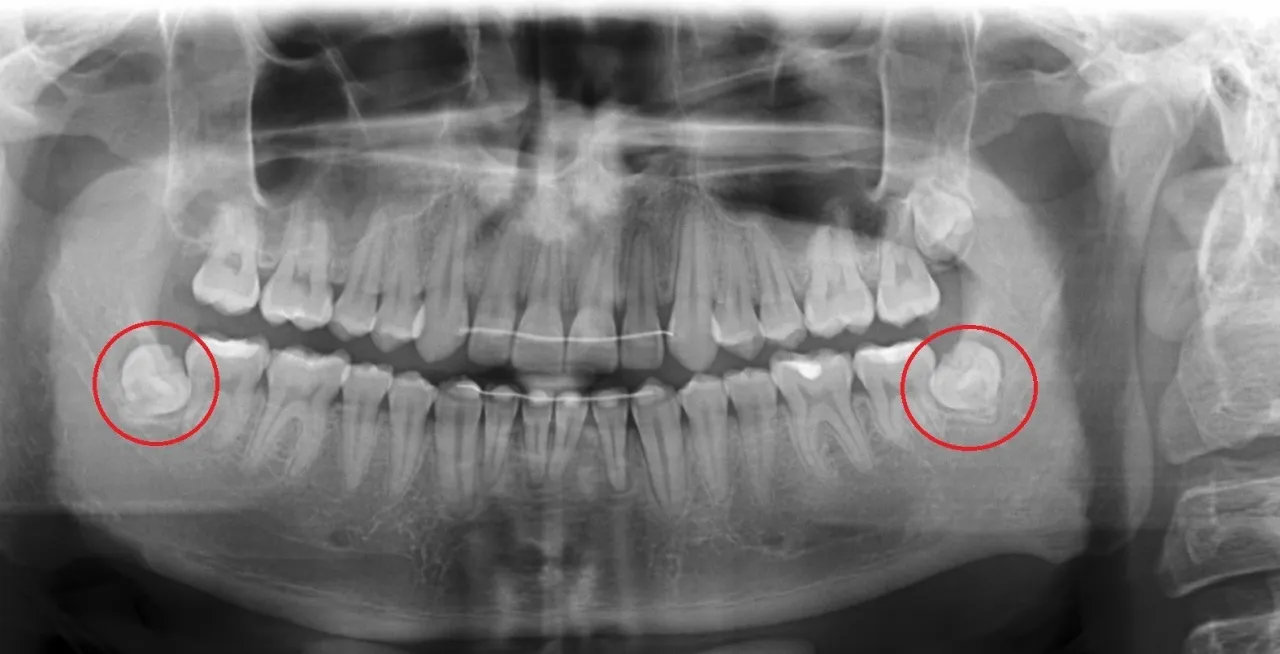

Rola zdjęcia RTG: Dlaczego bez pantomogramu nie da się podjąć decyzji?

W mojej praktyce zawsze podkreślam, że bez zdjęcia RTG, a zwłaszcza pantomogramu, nie da się podjąć odpowiedzialnej decyzji o usunięciu ósemki. To kluczowe narzędzie diagnostyczne! Pantomogram (zdjęcie panoramiczne) pozwala mi zobaczyć nie tylko sam ząb, ale także jego korzenie, położenie w kości, bliskość ważnych struktur anatomicznych, takich jak nerw zębodołowy dolny czy zatoka szczękowa. Dzięki temu mogę ocenić stopień trudności zabiegu i zaplanować go w najbezpieczniejszy sposób. To absolutna podstawa przed każdą ekstrakcją ósemki.

- Decyzja o usunięciu ósemki zawsze wymaga konsultacji ze stomatologiem lub chirurgiem szczękowym i wykonania zdjęcia RTG (pantomogramu).